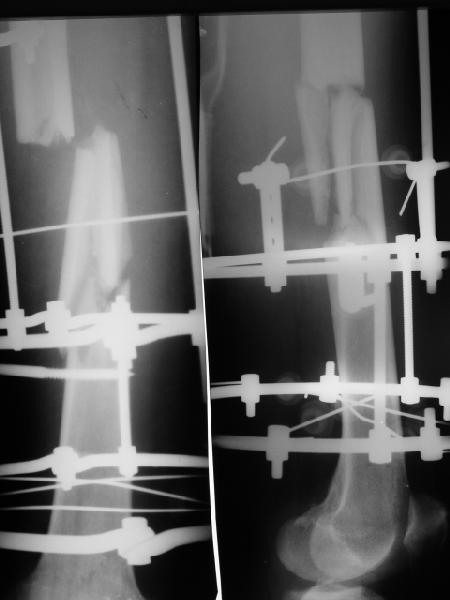

Парень 28 лет поступил с переломом 6едра уже в аппарате (см. снимок),

наложенном в Тобольске 6 недель назад. С двух строн еще переломы плюсневых костей, а с этой же стороны и дистального эпиметафиза большеберцовой кости, в гипсовых повязках до колена.Бедро намереваемся закрыто заштифтовать, но нету определенности - вводить гвоздь анте- или ретроградно (через колено)? Повязку сверху на этой голени малость подкоротили на всякий случай. Кроме как бросить монетку, чем определить выбор? Заранее спасибо.